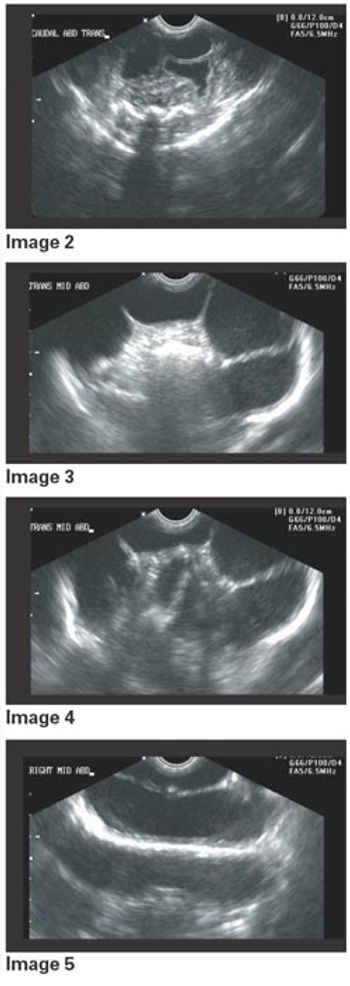

Signalment: Canine, Greyhound, 2.5 years old, female spayed, 65 lbs. Clinical history: The dog has a persistent urinary tract problem ? hematuria for at least one year according to the owner. The dog improves with antibiotics, but once finished, hematuria starts again. Therapy has included Clavamox.